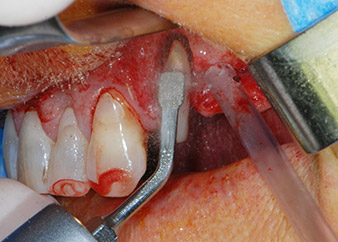

Un mes después, en el día de la intervención, el dolor y la inflamación se habían reducido al mínimo en la pieza 24, pero seguía habiendo una movilidad de clase II de Miller. Después de la apertura de los colgajos y de la limpieza del tejido infectado periapical y perirradicular, la extensión del defecto óseo quedó evidente (figuras 2 y 3).

En primer lugar, en un intento por gestionar el problema endo-periodontal, el resto de la superficie radicular se desbridó con cuidado con un equipo piezoeléctrico (Piezomed de W&H, utilizado con el inserto S1 con forma de espátula, concebido en un principio para la erosión de la pared lateral del seno) (figura 4). A continuación, el ápice se erosionó con el mismo instrumento para eliminar el tejido apical infectado residual y reducir las posibles ramificaciones accesorias del canal radicular (apicectomía) (figura 5). No fue necesario realizar un retrorellleno, puesto que la obturación ortógrada se acababa de revisar.